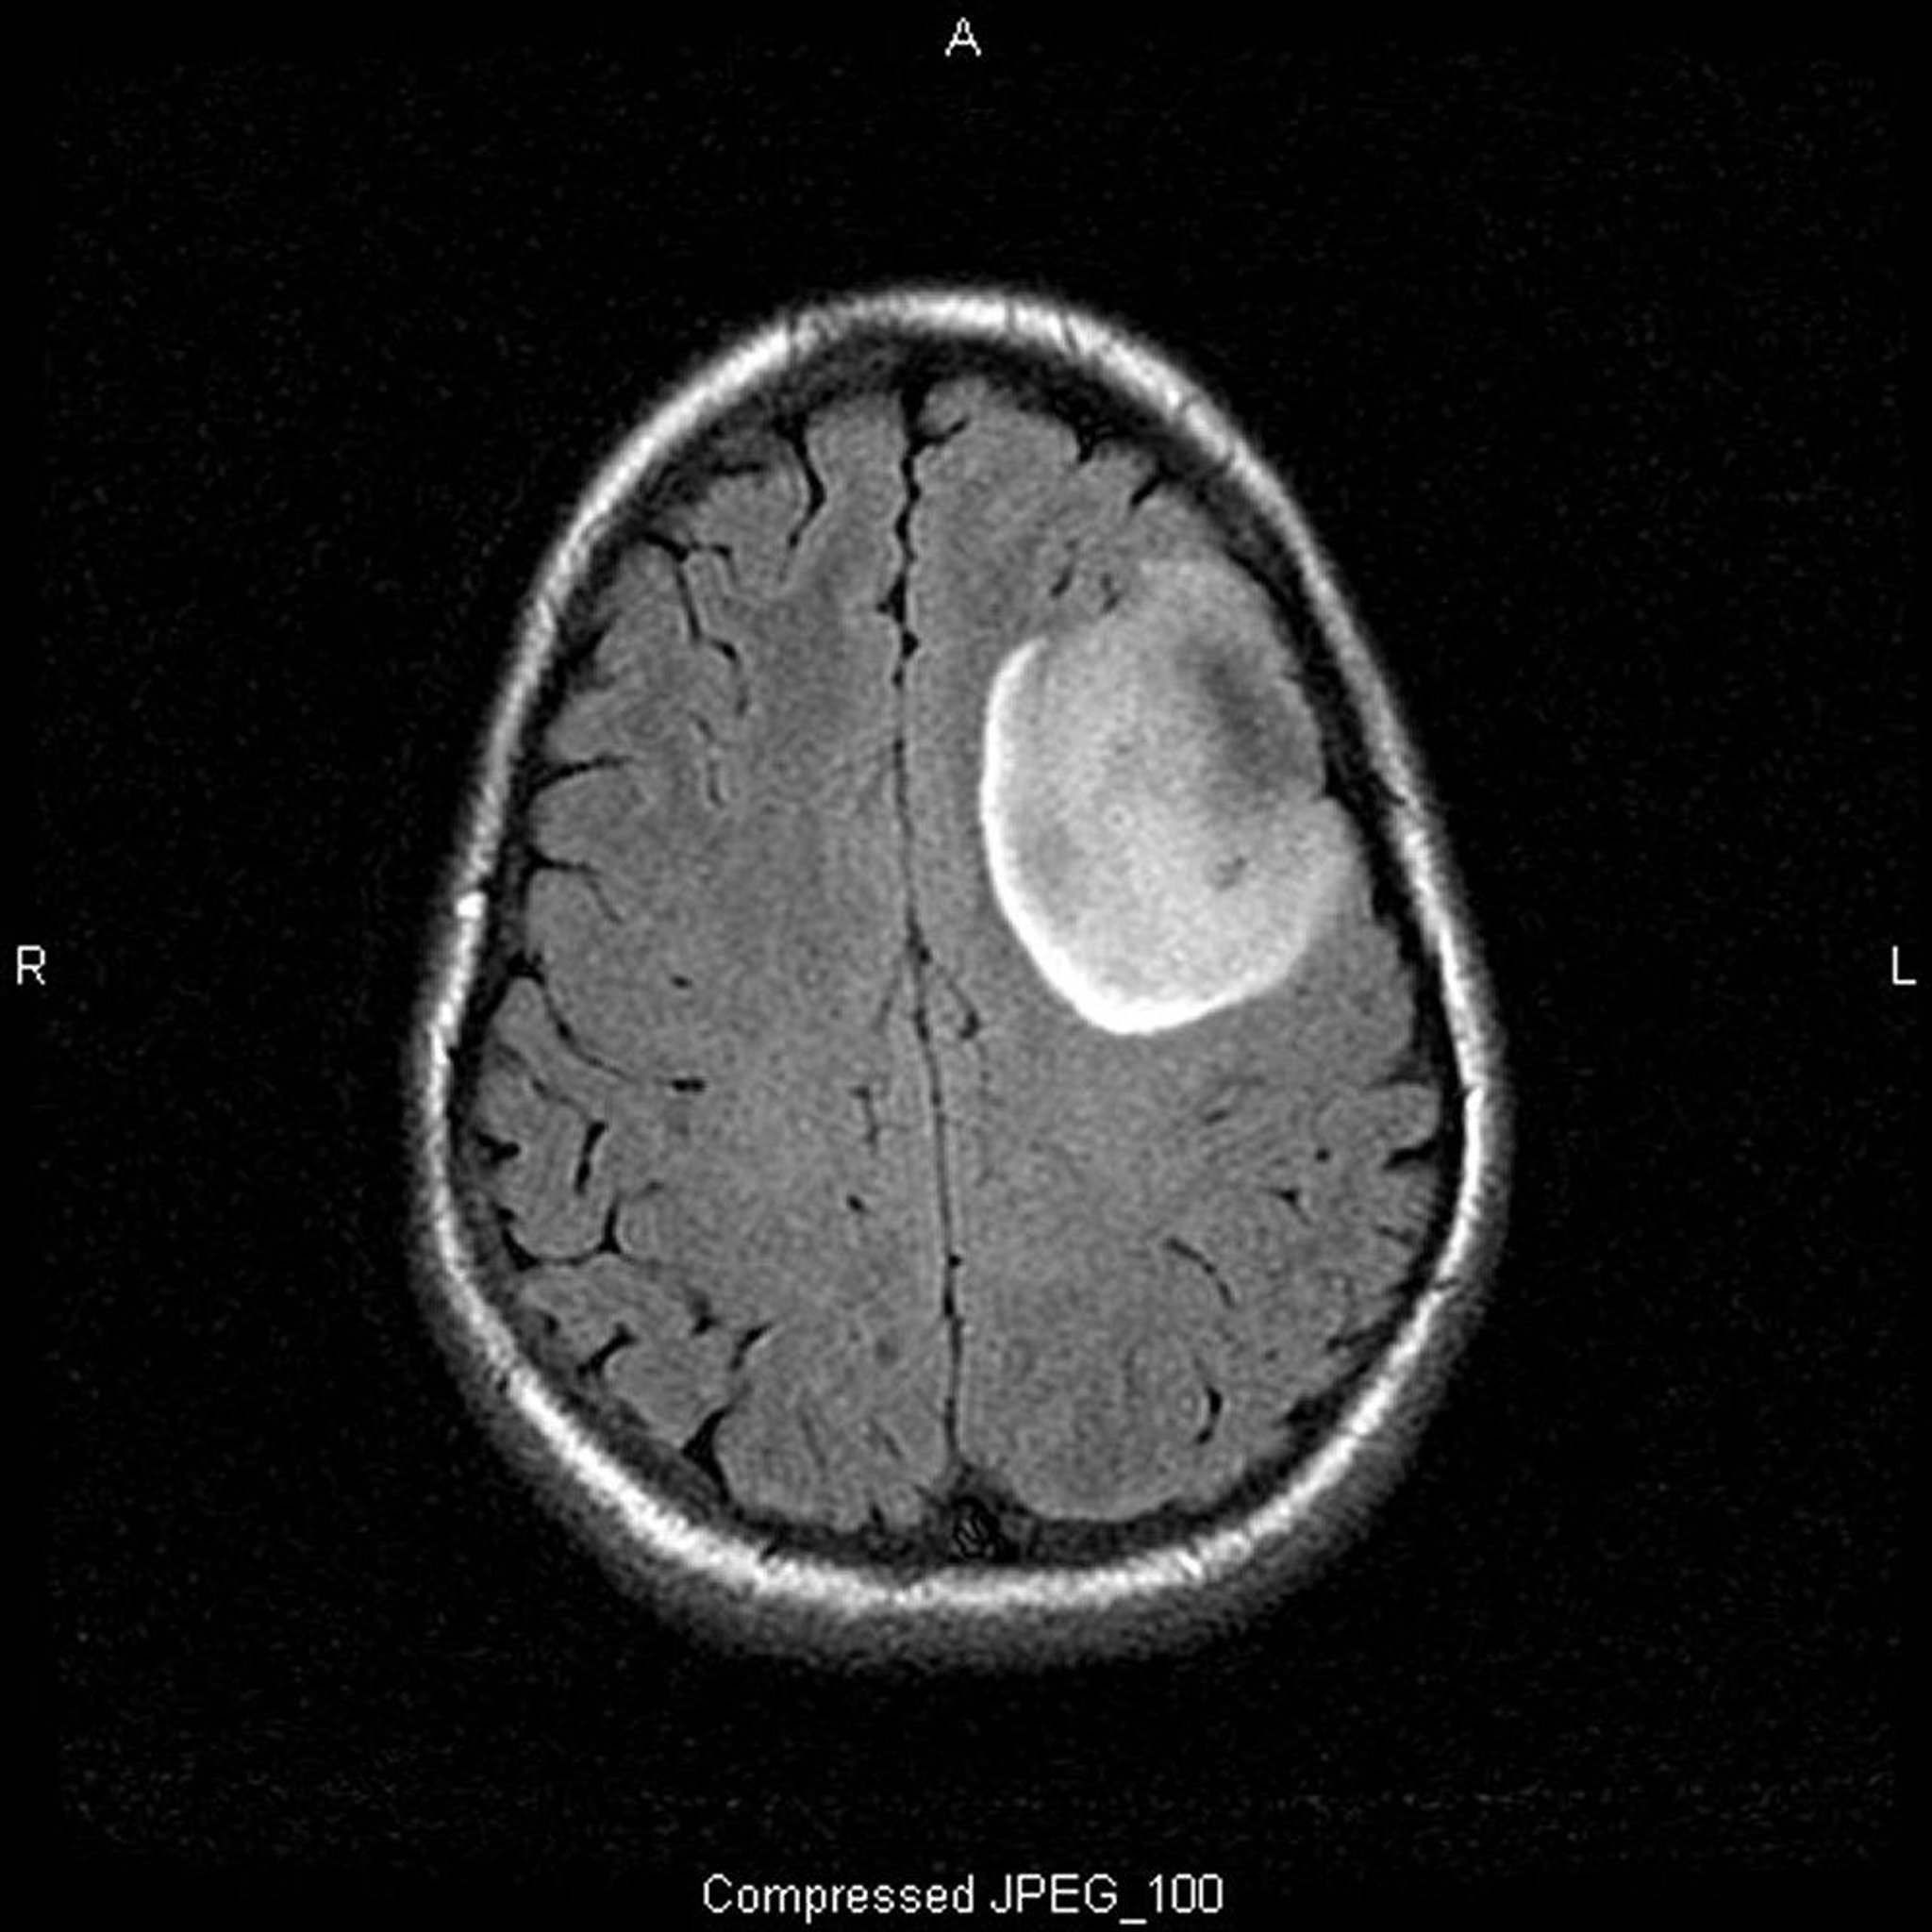

Oligodendroglioma, Low-Grade

This T2-FLAIR (fluid-attenuating inversion recovery) MRI scan shows a white signal, which may indicate a mass or edema. The left frontal signal is highly demarcated, suggesting a mass. Use of contrast does not enhance it. It is a low-grade (grade II) oligodendroglioma.

Image courtesy of William R. Shapiro, MD.